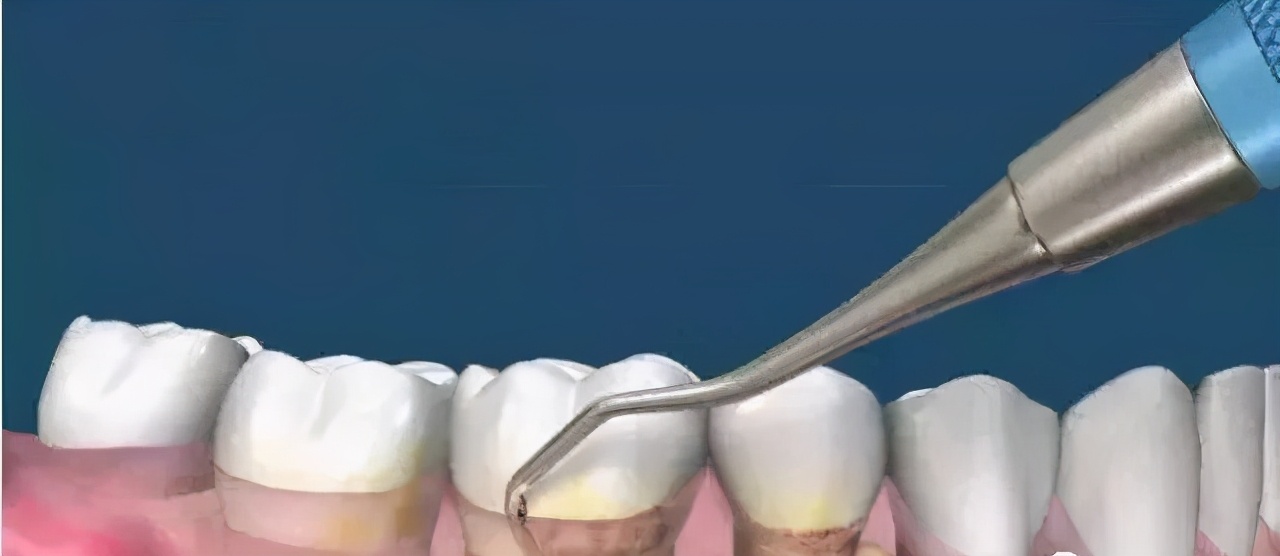

洗牙的目的在于——去掉牙结石!

有的人说:为什么能从嘴里抠出黄泥,或者是硬硬的物质。这些都是牙结石,它是由口腔中的钙以及细菌沉积造成的结果,并不会因为每天几次刷牙就能够解决。

口腔内无时无刻都会积攒大量的细菌,而它们随着时间的推移,好比“滴水穿石”一般,时间越久积累的程度也就越严重。此外,还会因为每次刷牙刷不到的地方,牙结石也会粘附在牙齿上,最终成为刷不掉的结石。